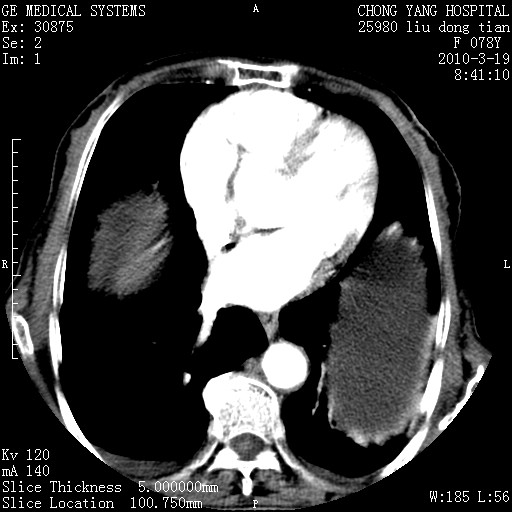

胆囊壁增厚并明显强化,胆囊癌伴多发转移瘤可能性大,淋巴瘤不除外,右肾囊肿,胸腹水.

胆囊有软组织影有强化,支持胆囊癌,肝脾、腹膜后淋巴结转移。

分开来讲:肝左叶、尾叶病灶有不均强化像肝癌;

胆囊增生性病变:胆囊癌,腺肌增生症,慢性胆囊炎;

腔静脉肝内段细小有无布加可能?

一元论最好了 淋巴瘤所致改变; 胆囊癌转移不像,胆囊周围肝组织清晰,肝癌淋巴结转移?三元论都不止。

最后报的胰头癌多发转移,脾脏单独考虑囊肿或淋巴管瘤。